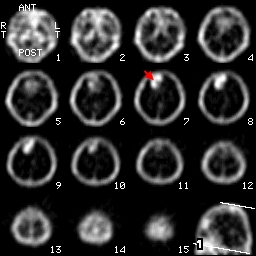

這是一個right frontal Lobe發現腫瘤的圖片,在這3個方向的切面中都能夠見到在大腦右前葉處出現了Tc-99m-DTPA的堆積影像,另外一張圖則是利用透視法所處理出來的3D影像,清楚的顯現出腫瘤的位置。

橫切面transverse